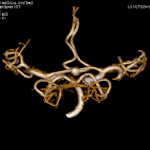

このボリュームCTにより早期発見から早期治療へつなげることが可能となり、心臓カテーテル検査の代替としても期待されます。

一部の症例以外では、従来の心臓カテーテル検査なしに血管狭窄の評価が可能であり、万が一、心筋梗塞になられた場合でも治療後の経過観察の心臓カテーテル検査は不要となります。

①安定した心臓撮影 : 心臓を5秒にて撮影(従来のマルチスライスCTでは約20秒間撮影)